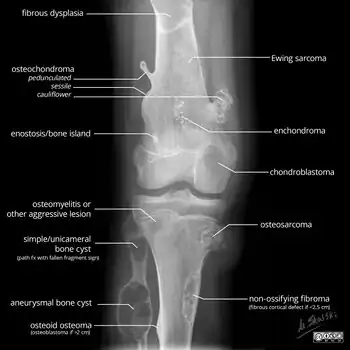

X-ray appearances of different types of bone tumors in < 30 years.